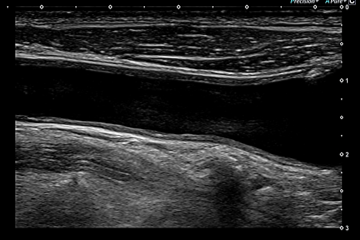

頚動脈エコー

頚動脈は、頚の部分にあり、心臓から脳へ血液を送る大きな血管のことです。頚動脈は脳へ血液を送る「内頚動脈」と、頭皮の方へ血液を送る「外頚動脈」とがあり、それら分かれ道となる部分を『頚動脈分岐部』といい、もっとも「動脈硬化」になりやすい部位といわれています。

頚動脈エコー検査では、頚動脈の状態を超音波によって検査するので、心筋梗塞や脳梗塞、大動脈解離などの命にかかわる病気が発症する危険度を事前に知ることができます。頚動脈エコー検査で頚動脈の動脈硬化(老化も含む)やアテローム硬化の状態を観察できます。